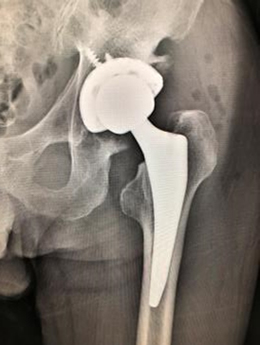

【人工膝関節】

- 術前

- 術後